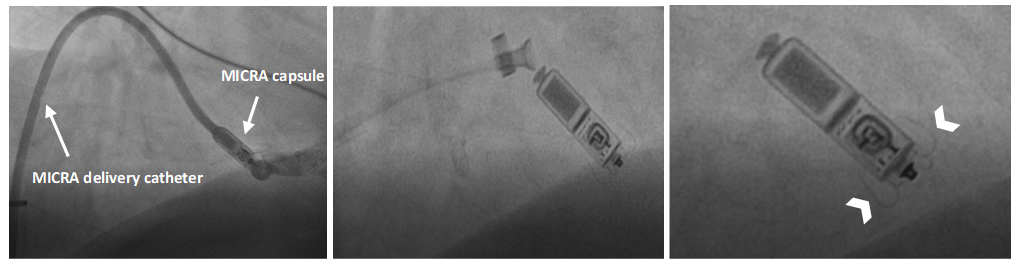

Both existing systems, Nanostim leadless cardiac pacemaker (LCP) (St. Jude Medical/Abbott Laboratories, Chicago, IL, USA) and Micra transcatheter pacing system (TPS) (Medtronic, Minneapolis, MN, USA), are implanted with similar technique in the catheterization laboratory under fluoroscopic guidance. Each device is mounted on its own dedicated introducer sheath (Fig. 1) and is advanced to the right ventricle (RV) percutaneously through the femoral vein. Once in the RV, contrast medium is injected through the sheath to help localize the best implant site. The main objective is to avoid the ventricular free wall where the risk of perforation is higher while targeting the apex or, whenever technically feasible, a septal position that has shown similar electrical performance [8]. Fixation is achieved by either a screw-in helix (Nanostim LCP) or successful attachment of at least 2 of 4 nitinol tines (Micra TPS). After electrical performance testing and confirmation of stability with a tug test, the device is released from the delivery system. Antibiotic prophylaxis and peri-procedural haemostasis are left at operator decision and centre-specific guidelines; evidence suggests that uninterrupted therapeutic anticoagulation represents a safe option associated with shorter in-hospital length of stay [9]. Flushing the introducer with heparinized saline solution, however, is recommended in all patients [10, 11]. Implantation technique steps are illustrated in Fig. 2.

Fig. 2.MICRA deployment steps. Left panel: Delivery catheter is advanced to the right ventricle and contrast medium is injected to confirm appropriate positioning. Middle panel: MICRA capsule is released, and a tug test is performed to verify stability. Right panel: MICRA device in place (arrowheads show nitinol tines).